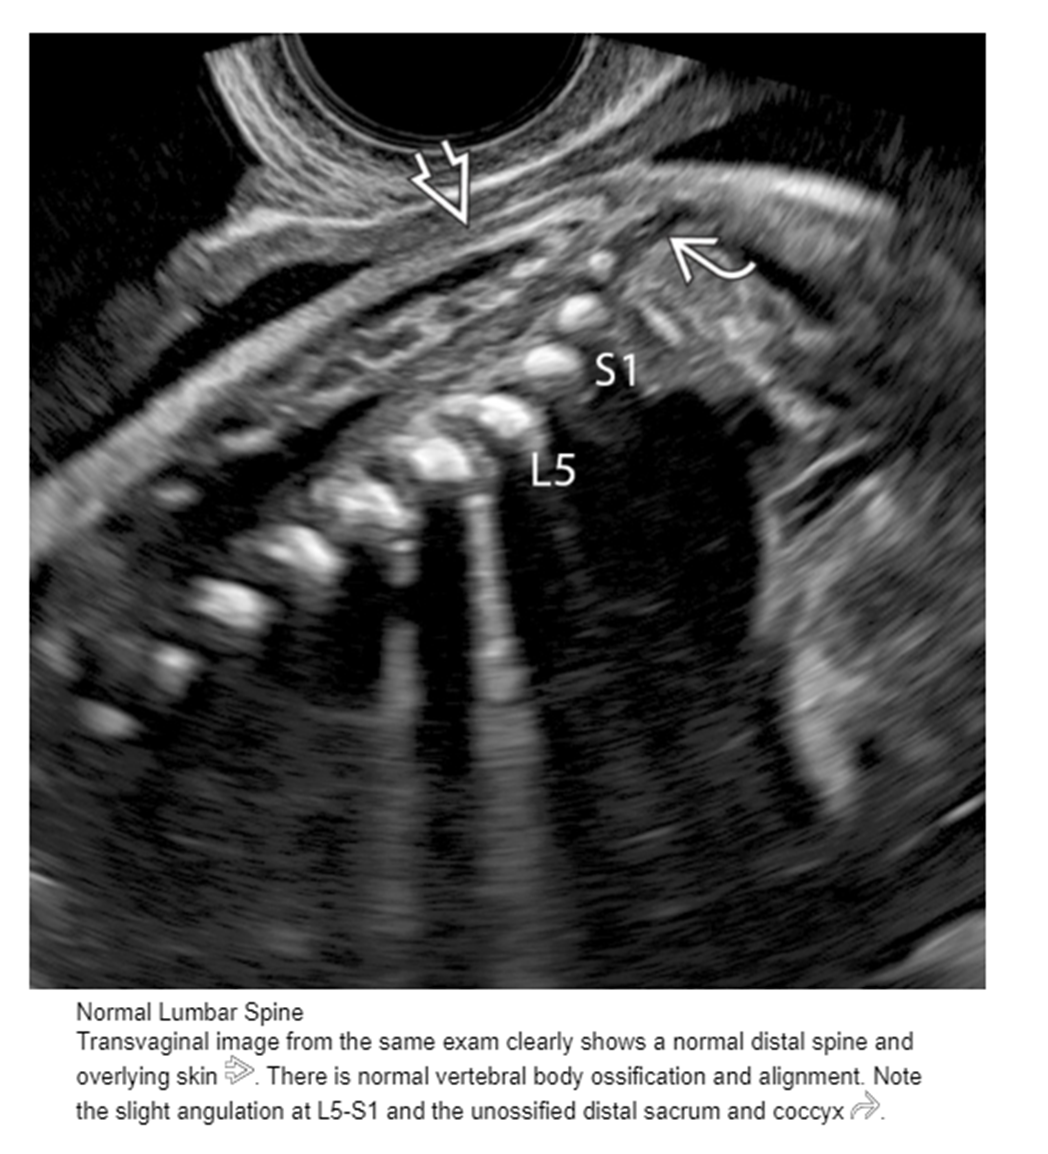

vertebrae numbers

7 cervical

12 thoracic

5 lumbar

5 sacral

in sagittal _______ should be imaged to ensure you are imaging the cervical spine

occipital bone

in transverse, the ______ should be visualized to ensure you are imaging cervical spine

fetal clavicles

thoracic spine, _____ or _____should be seen

heart or stomach

lumbar spine, ____ should be seen

kidneys

sacral spine, _____ is landmark

iliac crest

what is important to include in spine images

skin line